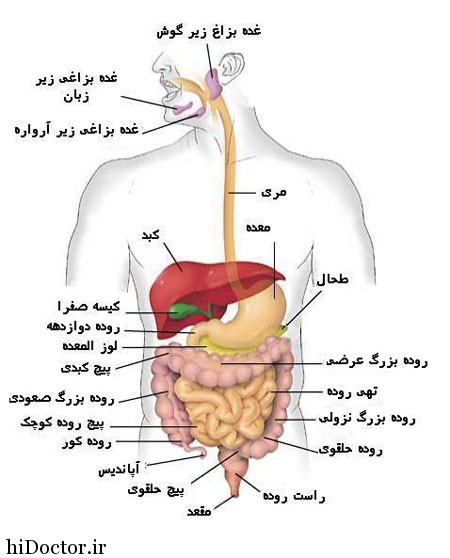

عکس داخل شکم انسان. در این همان طور که مشخص است شکم حالت بیضی شکل پیداکرده و این بیضی که کناره های شکم کشیده شده است. تعداد سلول های بدن انسان حدود ۳۷ ۲ تریلیون تخمین زده شده اند. Abdomen که در زبان عامه به غلط به آن دل نیز می گویند در آناتومی به قسمتی از تنه گفته می شود که مابین دیافراگم از بالا و سطح فوقانی لگن خاصره از پایین قرار دارد. ربات دیدنی ربات انساننمای چینی به صورت یک دختر جوان ساخته شده و جیا جیا نامگذاری شده است این ربات طوری برنامهریزی شده که میتواند صحبت کند و احساسات خود را از طریق تغییرات در چهره حالات.

شکل دوم شکم مادری را نشان می دهد که جنین دختر دارد. وحشت مادر از عکس سونوگرافی جنین داخل شکمش عکس. تصاویر جالب از داخل مغز و نخاع انسان آخرین نیوز. بدن انسان کل ساختار انسان است که سر گردن تنه سینه و شکم دو بازو و دست ها و دو ساق پا و پاها را شامل می شود.